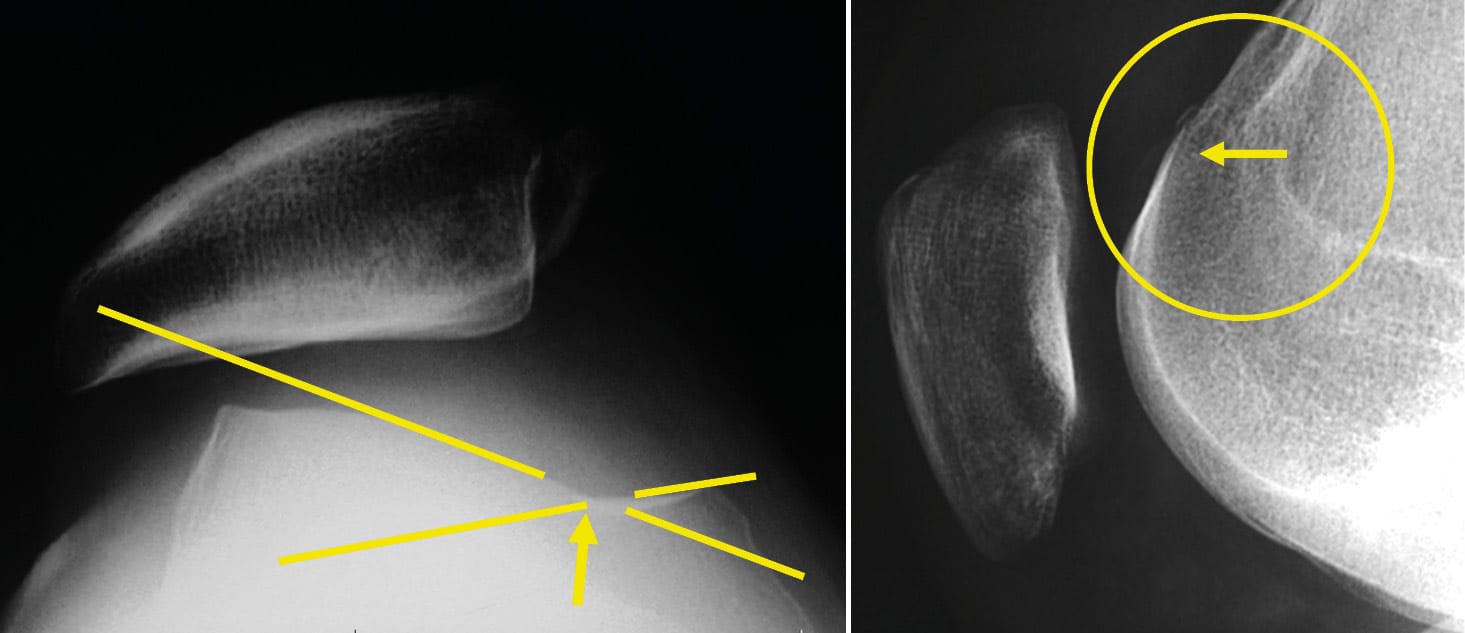

A good lateral X-ray of the knee meets specific criteria (Figure 14). It is performed at 30° of flexion with the two posterior condyles superimposed. To optimise this superimposition, a brief fluoroscopy may be performed. The patient can be lying on the X-ray table or in single-leg stance.

The axial view of both patellae must be performed with both knees flexed at 30° and no more, as is too often the case. Both knees are on the same cassette. We no longer request a series of views with the knee flexed at 60° and 90° or in external rotation.

The axial view (Figure 16) is conventionally performed at 30° of flexion. It does not account for the proximal part of the trochlea. The lateral X-ray allows for the analysis of the trochlea from its most proximal part down to the notch.

This is the true value of the lateral view: The analysis of the proximal portion, the upper part of the trochlea.

On this lateral radiograph (Figure 16), one can recognise the trochlear groove line but also the two condyles, lateral and medial. This trochlear groove line remains distant from the lines of the two condyles. In fact, these three lines are found on the axial view, with the medial and lateral facets of the trochlea as well as the trochlear groove line. The trochlear groove line always remains distant from the line of the two condyles, even in its proximal part.

Here is a very clear crossing sign (Figure 17) on the lateral radiograph. From this point upwards, the trochlea is flat or even convex. As the crossing occurs quite low on the trochlea, it is very dysplastic, and this can be diagnosed on the axial view at 30° of flexion.